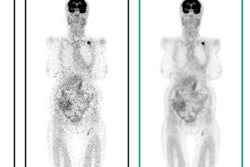

Founded by imaging researchers and AI developers from Stanford University, Subtle is developing AI algorithms aimed at enhancing the acquisition, reconstruction, processing, and analysis of medical images. The company is working on algorithms that could, for example, enable PET scans to be performed at just 1% of current radiotracer dose levels and facilitate the use of gadolinium-based contrast agents in MRI at just 10% of current dose levels.